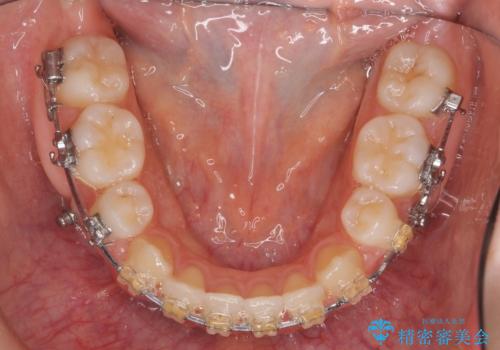

- ワイヤー矯正

臼歯の反対咬合は簡便なマウスピース矯正で治すのは難しいです。